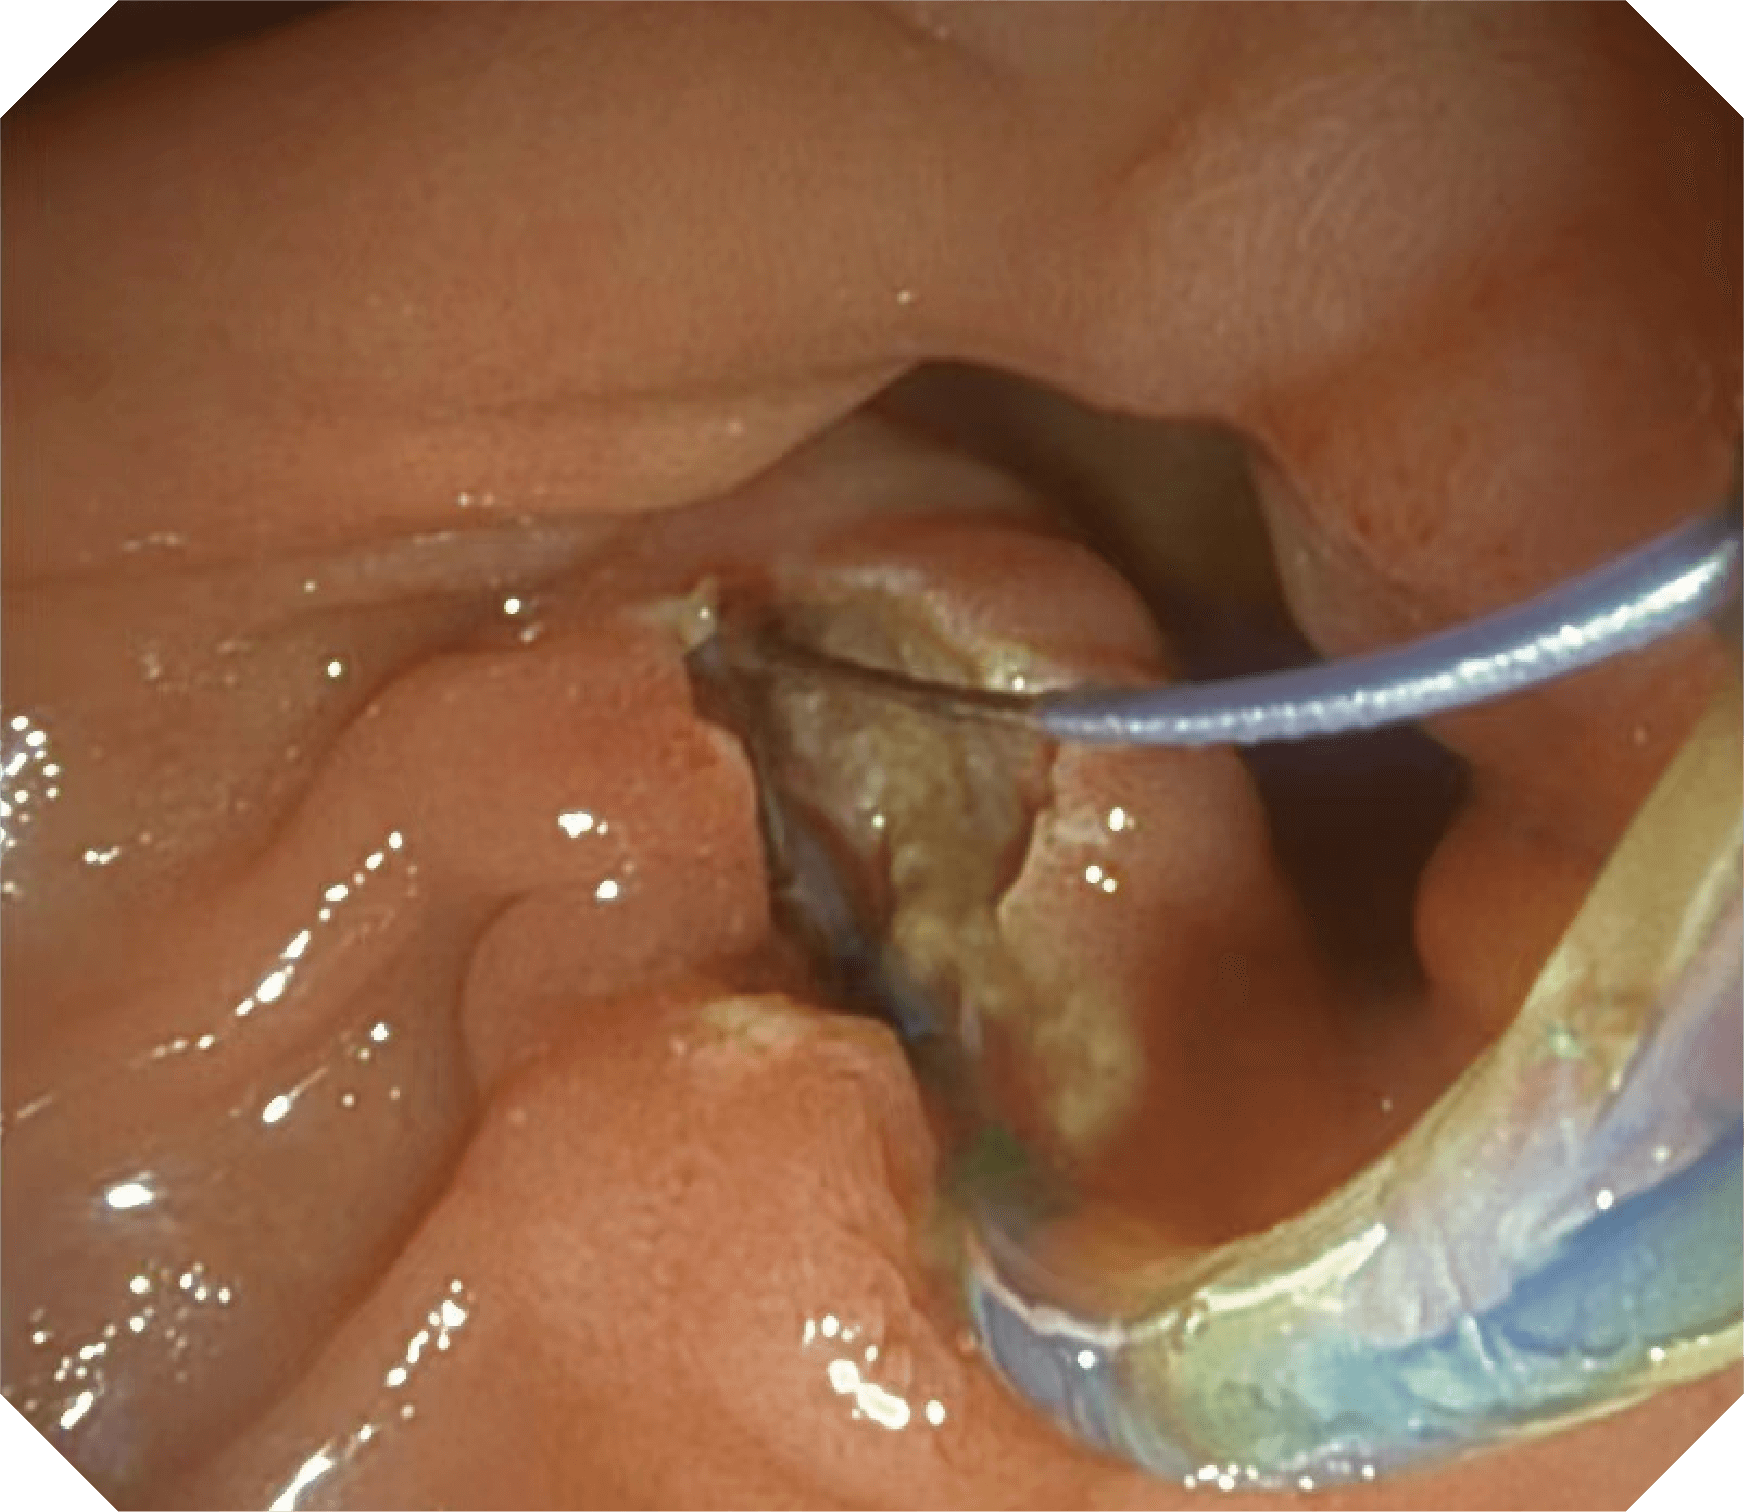

导丝机械锁紧功能

V槽设计提升导丝控制

优异的手术器械抬举性

更好的通过性,更稳定的镜体支撑力